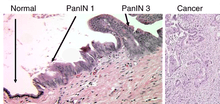

These cancers are thought to arise from several types of precancerous lesions within the pancreas. But these lesions do not always progress to cancer, and the increased numbers detected as a by-product of the increasing use of CT scans for other reasons are not all treated.[6] Apart from pancreatic serous cystadenomas (SCNs), which are almost always benign, three types of precancerous lesion are recognized.

The first is pancreatic intraepithelial neoplasia. These are microscopic abnormalities in the pancreas, which are often found in autopsies of people with no diagnosed cancer. These may progress from low to high grade and then to a tumor. More than 90% of cases at all grades carry a faulty KRAS gene, while in grades 2 and 3 damage to three further genes – CDKN2A (p16), p53 and SMAD4 – are increasingly often found.[4]